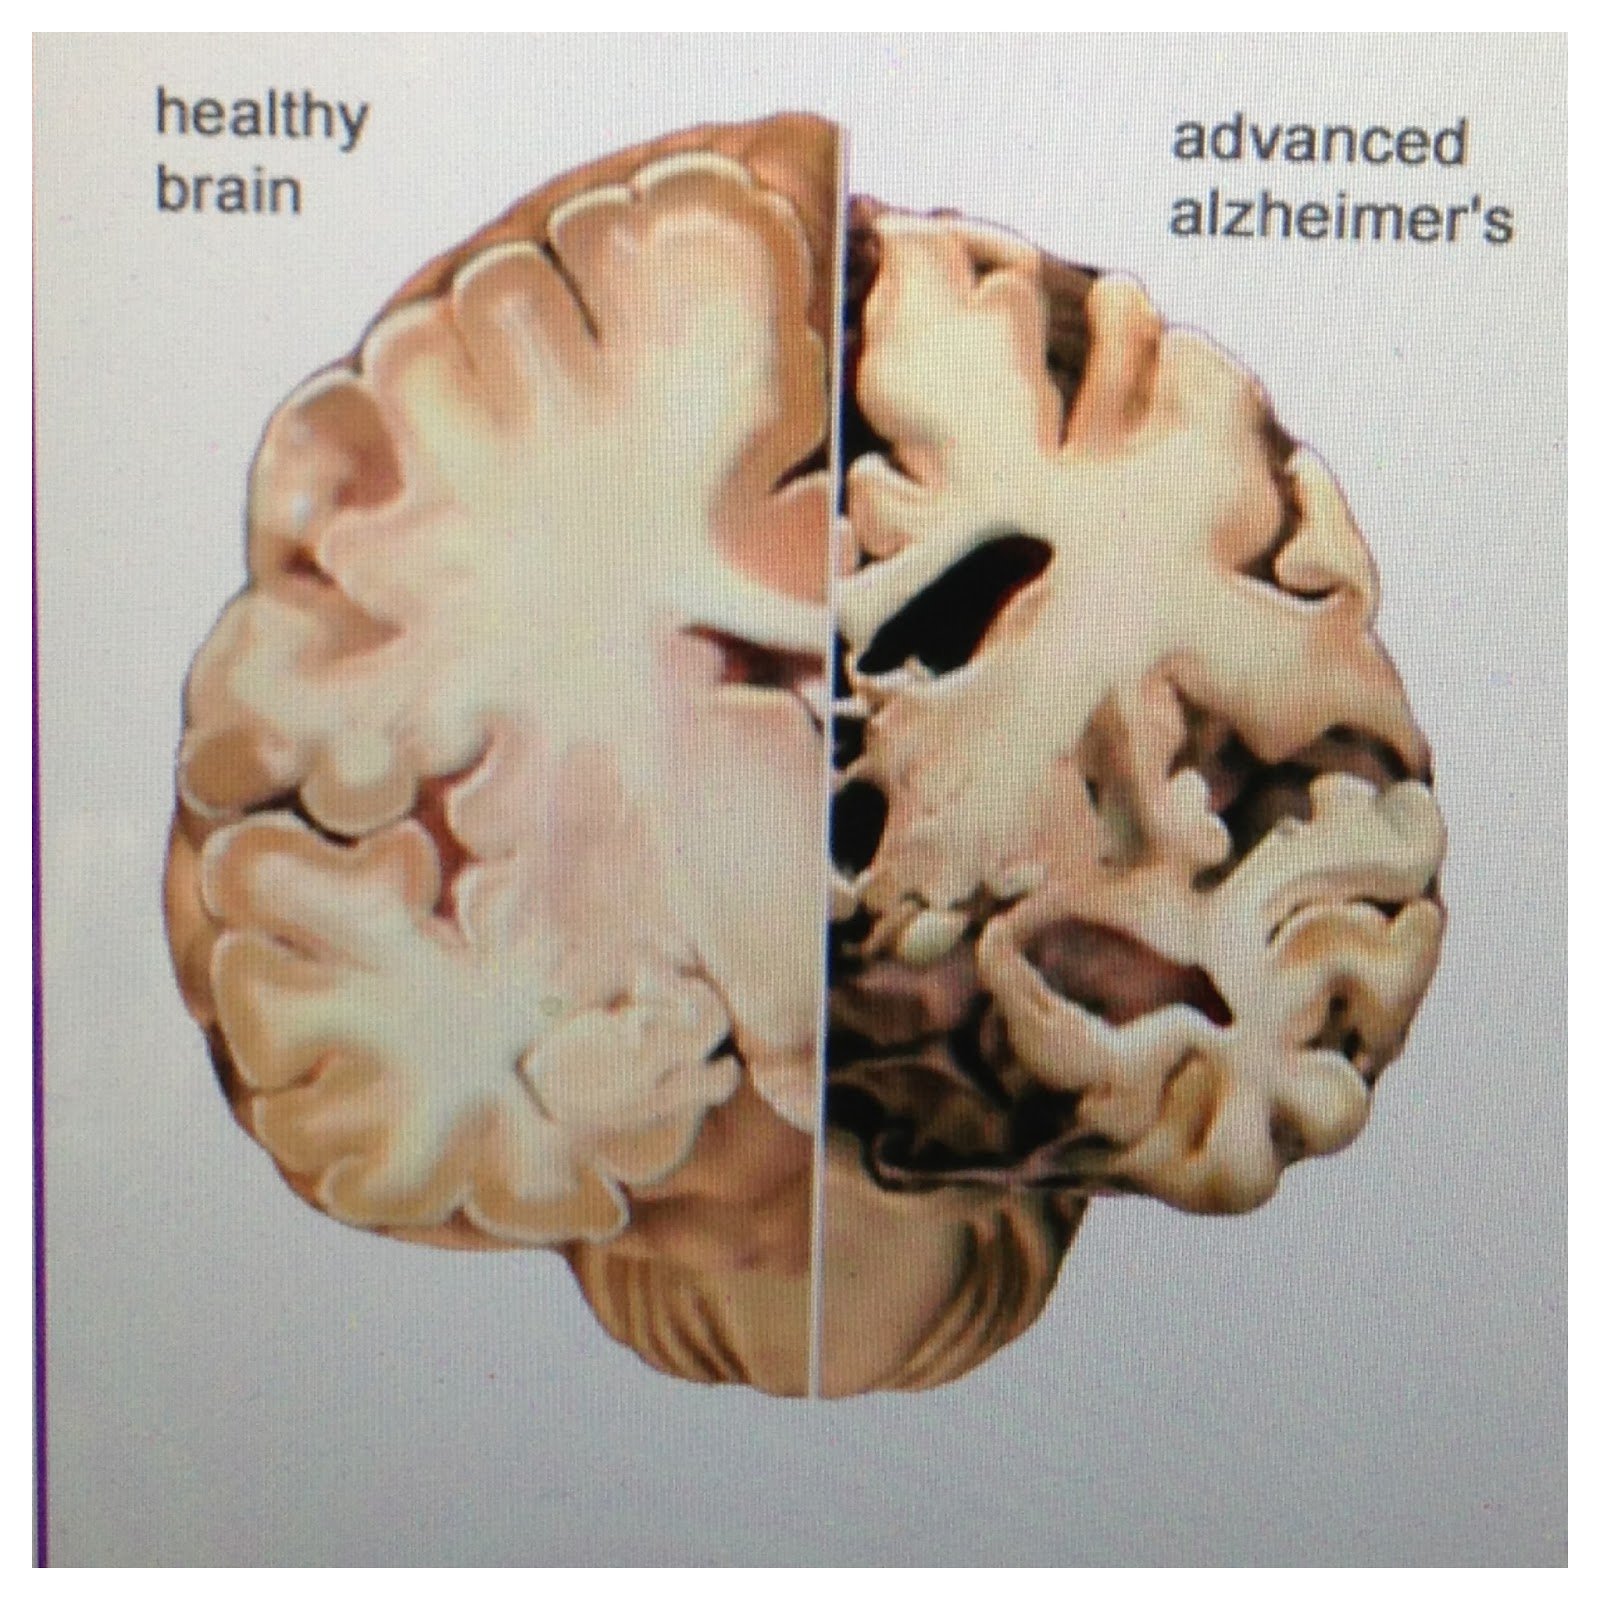

What Does The Brain Look Like With Dementia – DementiaTalkClub.com

The Healthy Brain (left) and the Alzheimer’s Brain (right) | Download …

Nervous system: Alzheimer’s Disease and Strokes – Classroom Partners

DEMENTIA Alzheimer Disease Memory Loss Brain Damage Medicine Health …

What is Dementia? Dementia vs Alzheimer’s Disease